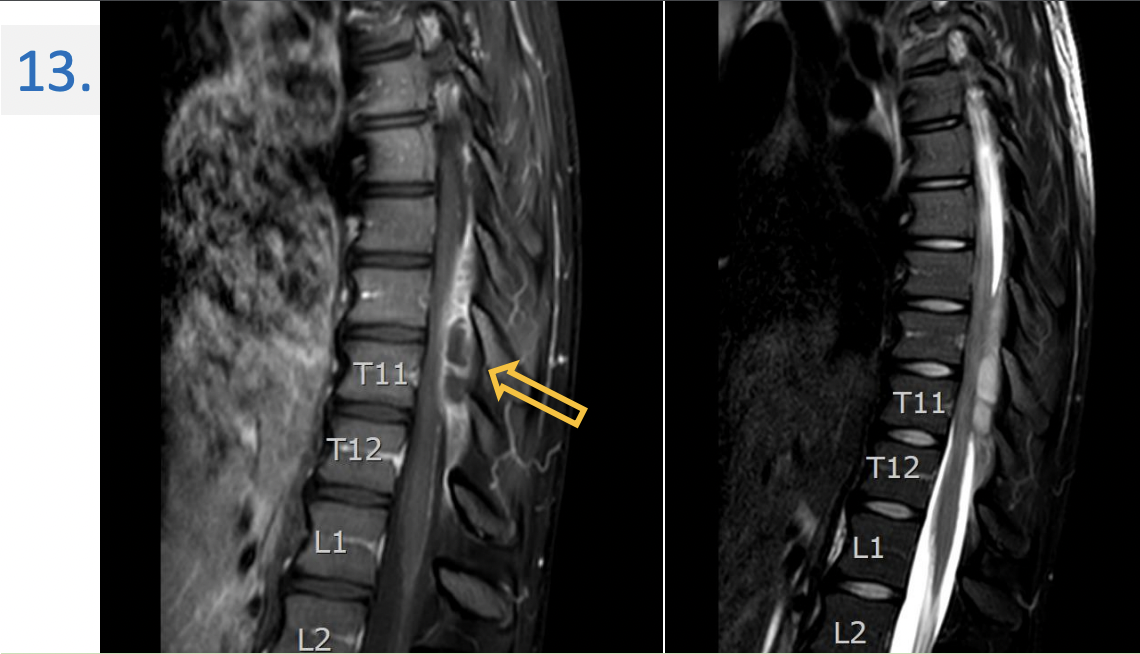

13